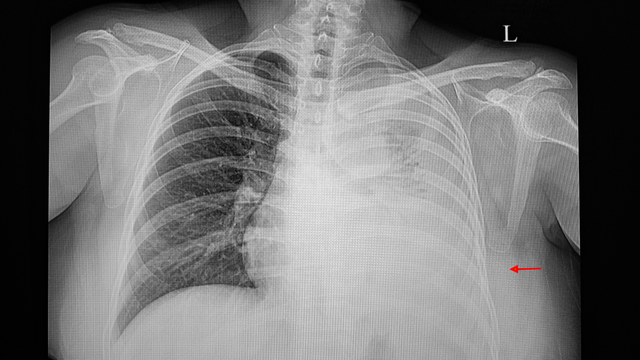

Bệnh phổi